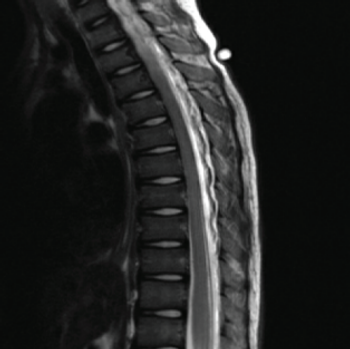

An 11-year-old boy with a history of asthma and allergic rhinitis presented to the emergency department (ED) with worsening fatigue, minimal responsivity to external stimuli, and diffuse muscle weakness for 2 months.